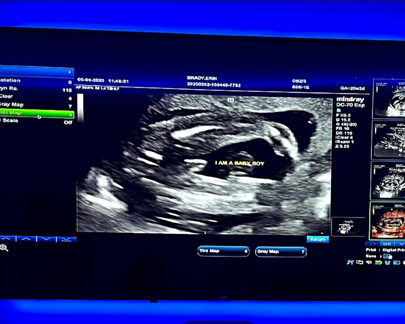

- Reveal gender at the appropriate stage

Gender Scan (15 Weeks onwards) : £65 £59

Celebrate this special moment with a thoughtfully designed twin gender reveal experience.